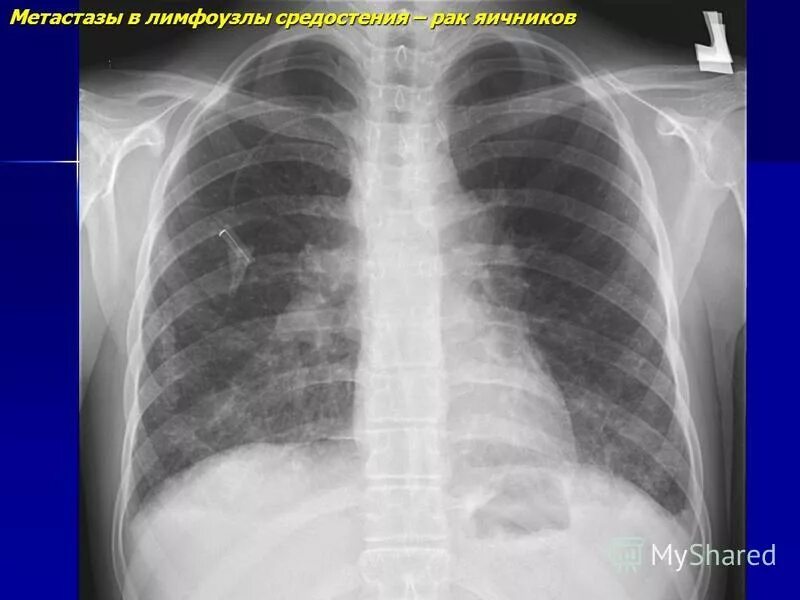

В лимфоузлах метастазы выживаемости